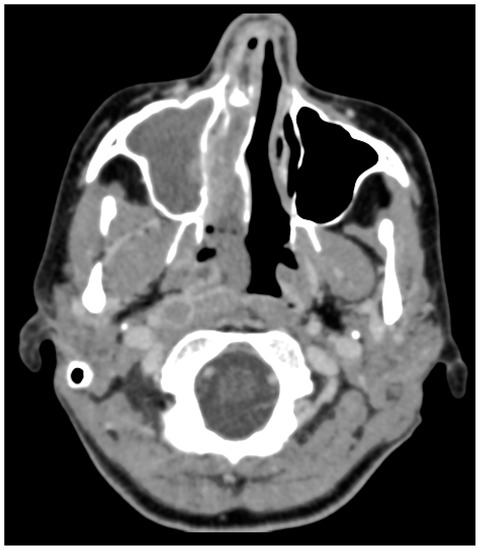

A previously healthy middle-aged woman initially presented to an outside hospital Emergency Room with the complaint of headache and right sided sinus/facial pressure. Computed tomography scan (CT) brain at that time showed complete opacification of the right maxillary, ethmoid, and sphenoid sinuses (Figure 1). She was presumptively diagnosed with acute on chronic sinusitis and prescribed a course of oral antibiotics, oral steroids, and intra-nasal steroids. Approximately two weeks after this presentation, she had a breast biopsy for a newly noted mass, the pathology of which was consistent with poorly differentiated malignant neoplasm.

Figure 1. Prehospitalization computed tomography scan (CT) Brain without Contrast, axial view. Initial CT obtained by primary care physician, which demonstrates complete opacification of the right ethmoid and sphenoid sinuses. Abbreviations: A = anterior; P = posterior.